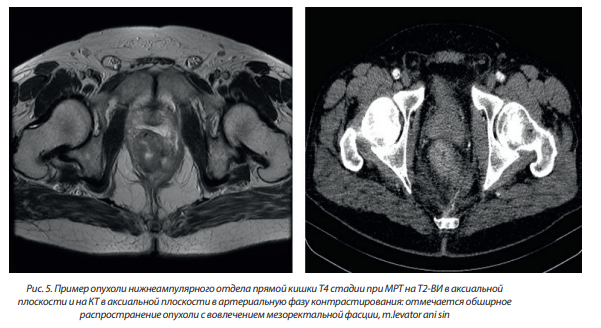

– Т4b — инвазия в другие тазовые органы.

Примеры опухолей различной Т стадии приведены на рис. 3–5.